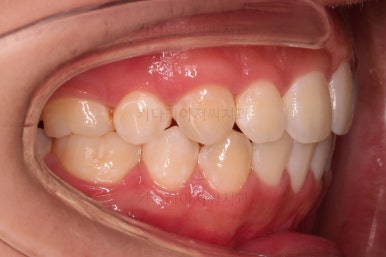

종료 시의 사진들을 전후 비교해 보겠습니다.

입매가 좋아졌고 입을 다무는 편안함도 좋아졌으며 치열이 가지런해졌으며 웃을 때 보이는 치열의 느낌도 좋고 교합도 잘 마무리 되었네요.